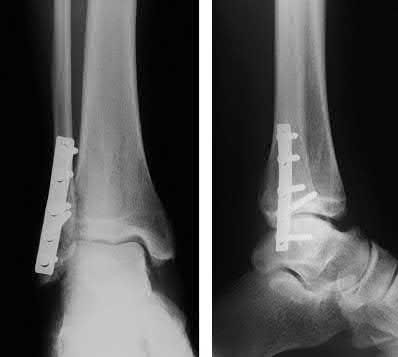

A 25-year-old male sustains an ankle fracture dislocation and undergoes open reduction and internal fixation. He returns to clinic five months following surgery complaining of continued ankle pain and instability with weight bearing. His immediate post-operative AP radiograph is seen in Figure A. Which of the following could have prevented this patient from developing persistent pain?

The patient presents with continued ankle pain and instability following open reduction and internal fixation. The radiograph in figure A demonstrates inadequate restoration of fibular length, likely leading to continued tibiotalar instability.